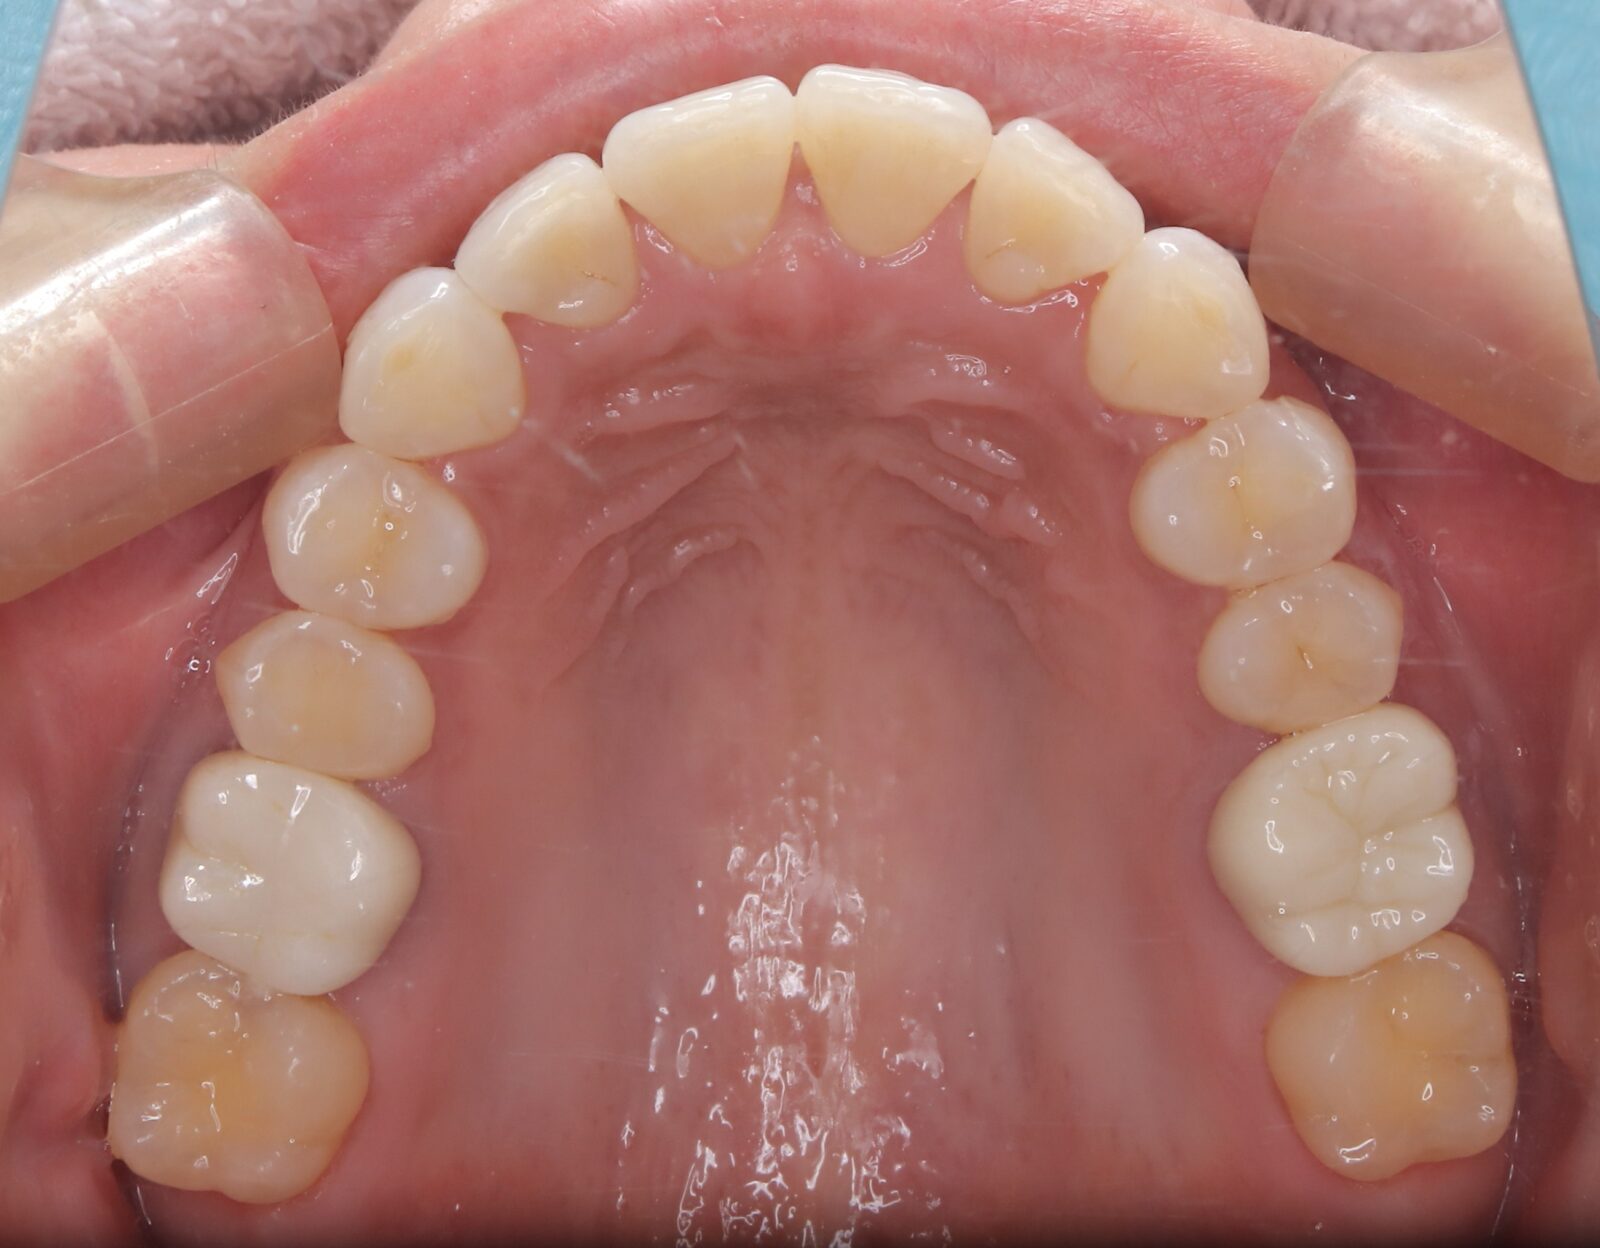

インビザライン(全体矯正)+ホワイトニングコースの症例

歯の裏に歯が隠れてしまっていたため、全体矯正(非抜歯+遠心移動)で美しく改善。

・費用:935,000円(税込)

・治療期間:30ヶ月

・通院回数:30回

・35歳女性

-リスクと副作用-

・長時間マウスピースを装着するため、むし歯や歯周病のリスクがある。治療後はリテーナーを装着しないと後戻りしてしまうリスクがある。

・ホワイトニング剤の影響で知覚過敏が起こる可能性がある。色が徐々に戻る可能性がる。